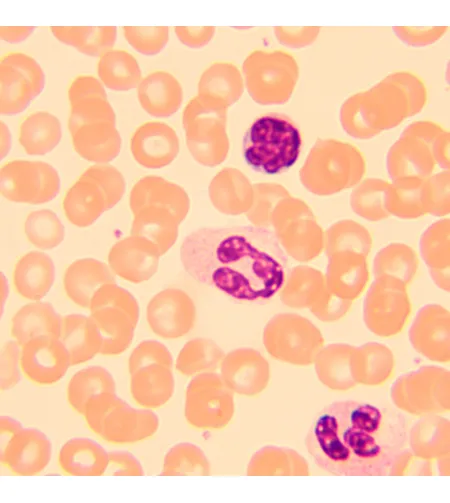

MAGUS Bio 250B biological microscope is an optical instrument used for studying thin transparent and translucent objects. Brightfield microscopy in transmitted light is the main microscopy technique. The microscope can be equipped with additional accessories for using darkfield, phase contrast, and polarization techniques. High-quality optics with additional options to expand its capabilities, easy-to-use mechanics, and smart design make this microscope an excellent choice for lab work, research, and teaching.

| Application | laboratory/medical |